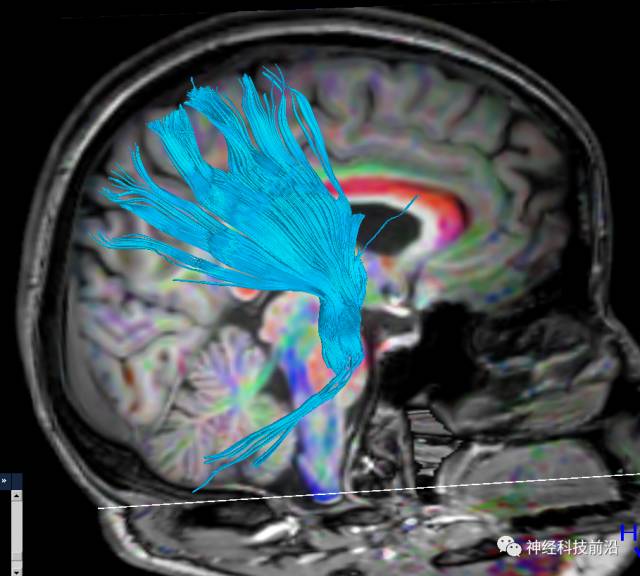

下面为皮质脊髓束的走形及位置